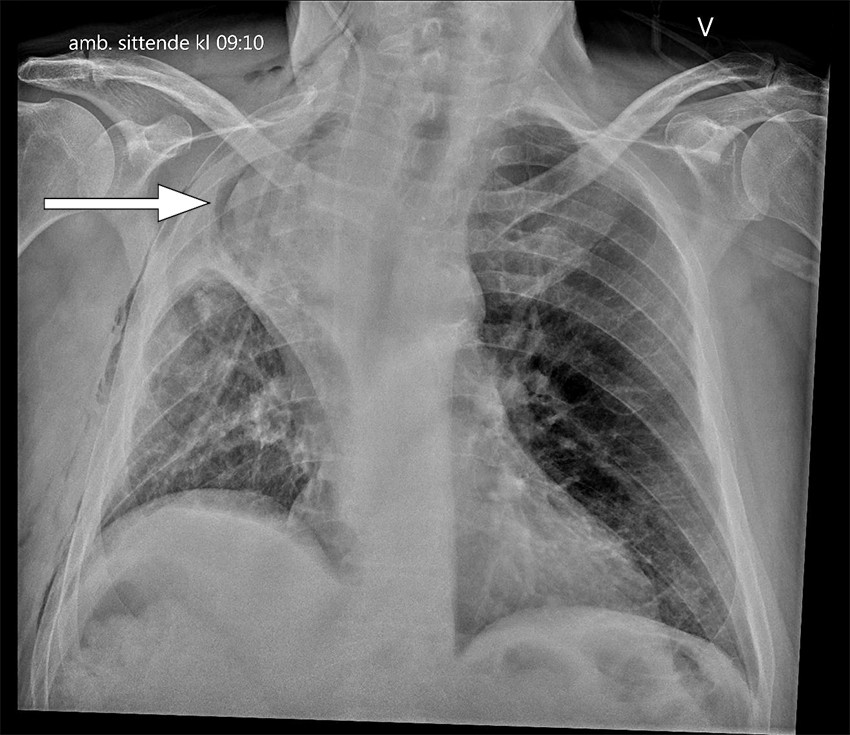

Rutinemessig postoperativ røntgen toraks viste atelektasepregede fortetninger i høyre lunges midtlapp. Det forelå også en liten høyresidig pneumotoraks og små mengder pleuravæske på samme side, som man kunne forvente etter operasjonen. Kontroll med røntgen toraks første postoperative dag viste økte fortetninger i øvre halvdel av høyre hemitoraks, som kunne være uttrykk for forverret atelektase, pleuravæske eller hemotoraks (figur 1). Pasienten var respiratorisk ubesværet og hadde god kapillær oksygenmetning på 96–98 % med oksygentilskudd 2 L/min på nesekateter. Det forelå ingen kliniske infeksjonstegn.

Grunnet tettere oppfølging ble røntgen toraks utført senere samme dag. Denne viste ikke vesentlig endring. Pasienten ble derfor henvist til CT-undersøkelse for videre diagnostikk. CT toraks med intravenøst kontrastmiddel utført på kveldstid samme dag viste en apikalt lokalisert midtlapp med utbredte mattglassfortetninger og områder med konsolidering samt fortykkede interlobulære septa (figur 2). Midtlappen fremsto som nærmest fullstendig devaskularisert. Proksimale midtlappsbronkus var obliterert, og transversale snitt viste subtilt virveltegn (swirl sign) i midtlappen som tegn på vridning. Fra radiologisk hold ble det reist mistanke om torsjon av midtlappen.